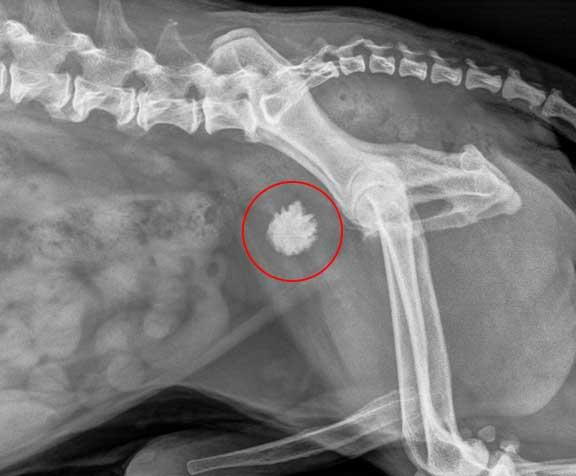

🧱 What Are Bladder Stones?

Bladder stones are hard mineral deposits that form in the bladder, similar to kidney stones in humans. They can vary in size and number, and they’re often painful or uncomfortable for your pet.